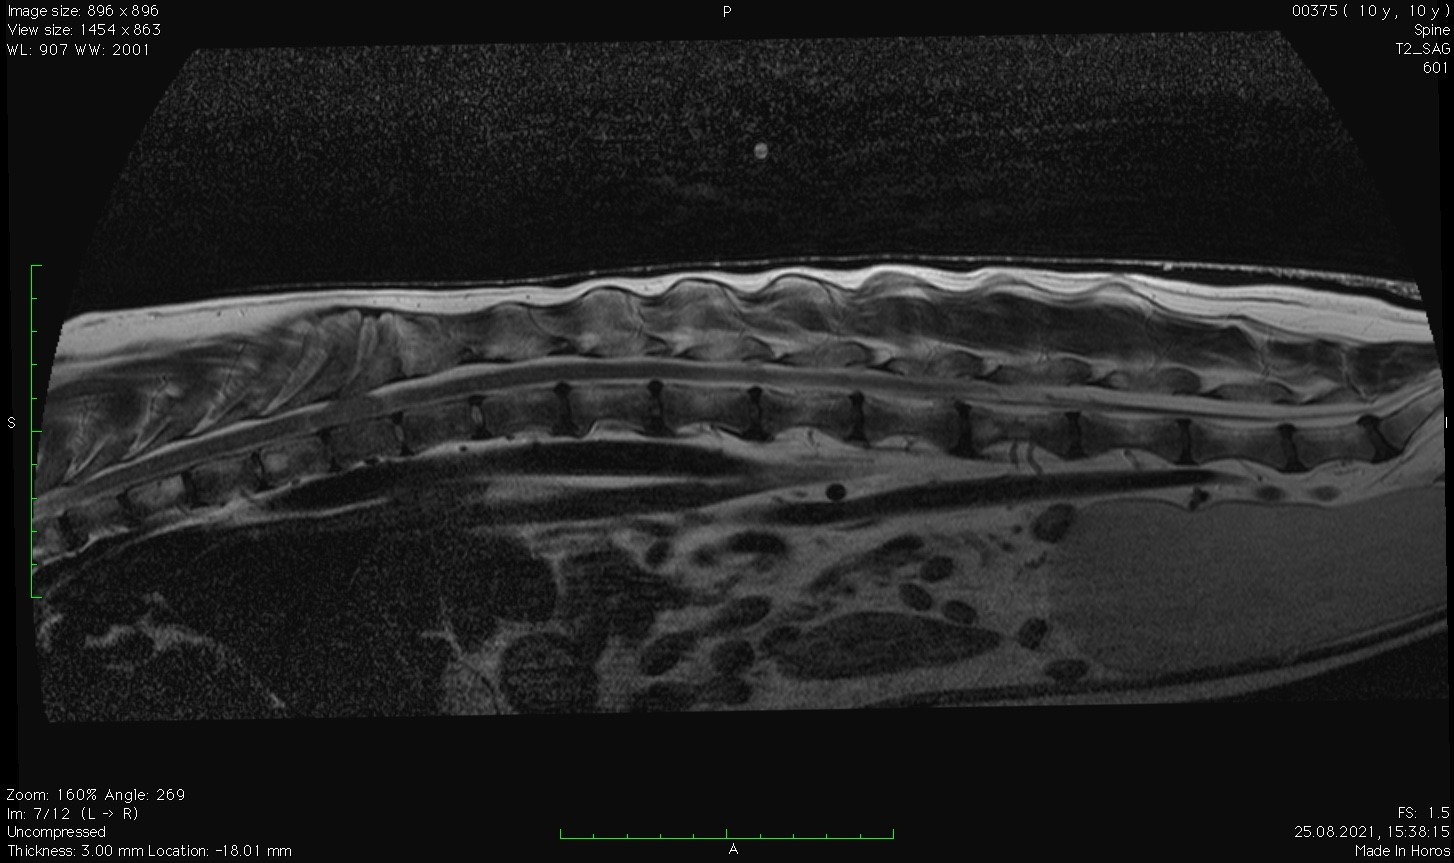

Заключение МРТ:

Признаки очагового образования с накоплением контраста в СМК на уровне Th10 (правая сторона) размером 2,2 х 2,3 см с поражением позвонка, окружающие ткани, выраженной компрессией СМ. С левой стороны на данном уровне отмечается артефакты. На уровне Th12-L2, L6-S1 отмечаются протрузии дисков.